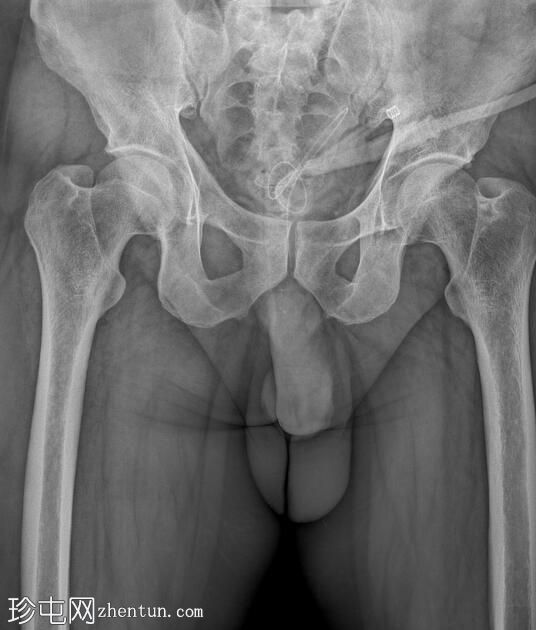

冠状位

斜位

逆行尿道造影显示球部近端尿道存在长段狭窄,造影剂广泛渗入阴茎静脉丛和盆腔静脉。

阴茎尿道外观正常。

造影剂已开始充盈膀胱。

该患者尿流细弱,表现为球部尿道长段狭窄。造影剂渗入与注射时施加的压力有关。